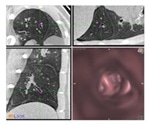

NTM lung infections

Getting drugs to bugs in NTM lung infections: an interview with Dr Jakko van Ingen